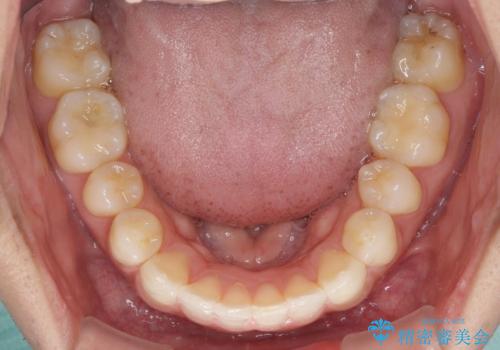

- 前歯のデコボコを治したいとのことで来院された患者様です。

上下顎ともに歯列全体の後方移動とIPR(歯と歯の間を削る)によってデコボコが解消するように設計し、インビザラインにより治療を行うこととしました。

毎日22時間以上しっかりとマウスピースを装着していただいたので、スムーズに治療が進みました。歯と歯の間を削ることでうまくスペースコントロールでき、1年強で終えることができました。